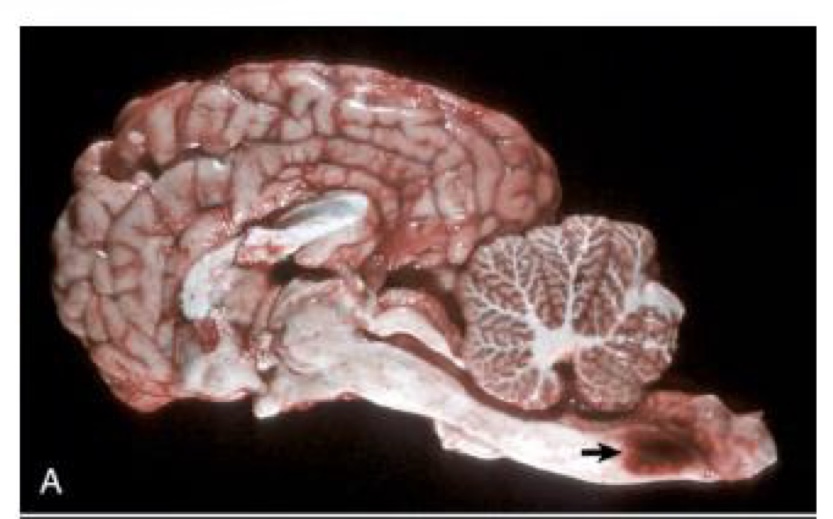

what is this?

ependymoma → third ventricle contains a moderately well demarcated expansile mass that has invaded normal tissue ventral to it; moderate hydrocephalus in both lateral ventricles